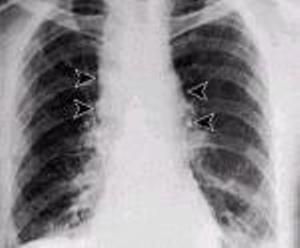

1. 肺炭疽:初期症狀象感冒,數日後病情急劇加重,發展成嚴重的肺炎。本病常續發炭疽腦膜炎,表現為劇烈頭痛、嘔吐、昏迷、神志不清,有明顯腦膜刺激症狀。該型病死亡率極高,達90%以上。